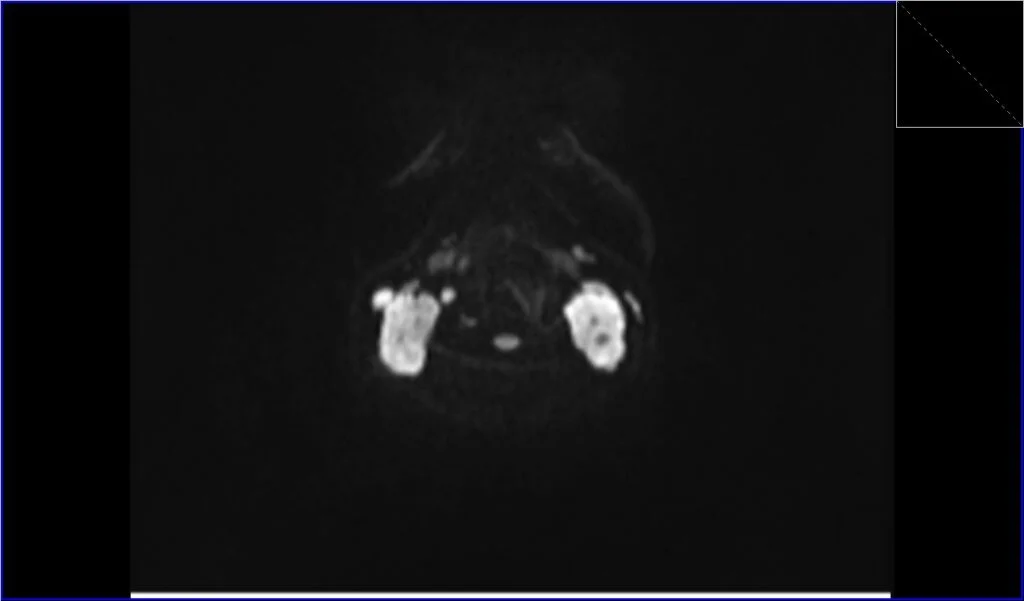

Diffusion-Weighted Imaging (DWI): DWI assesses the diffusion of water molecules within tissue. Lymphomatous tissue often restricts water diffusion due to high cellularity and increased nucleic content. On DWI, lymphoma can appear as areas of high signal intensity, and on the corresponding Apparent Diffusion Coefficient (ADC) maps, they will show low signal intensity, indicating restricted diffusion. This can help differentiate lymphoma from other neck masses.

DWI axial b800 image shows Lymphoma